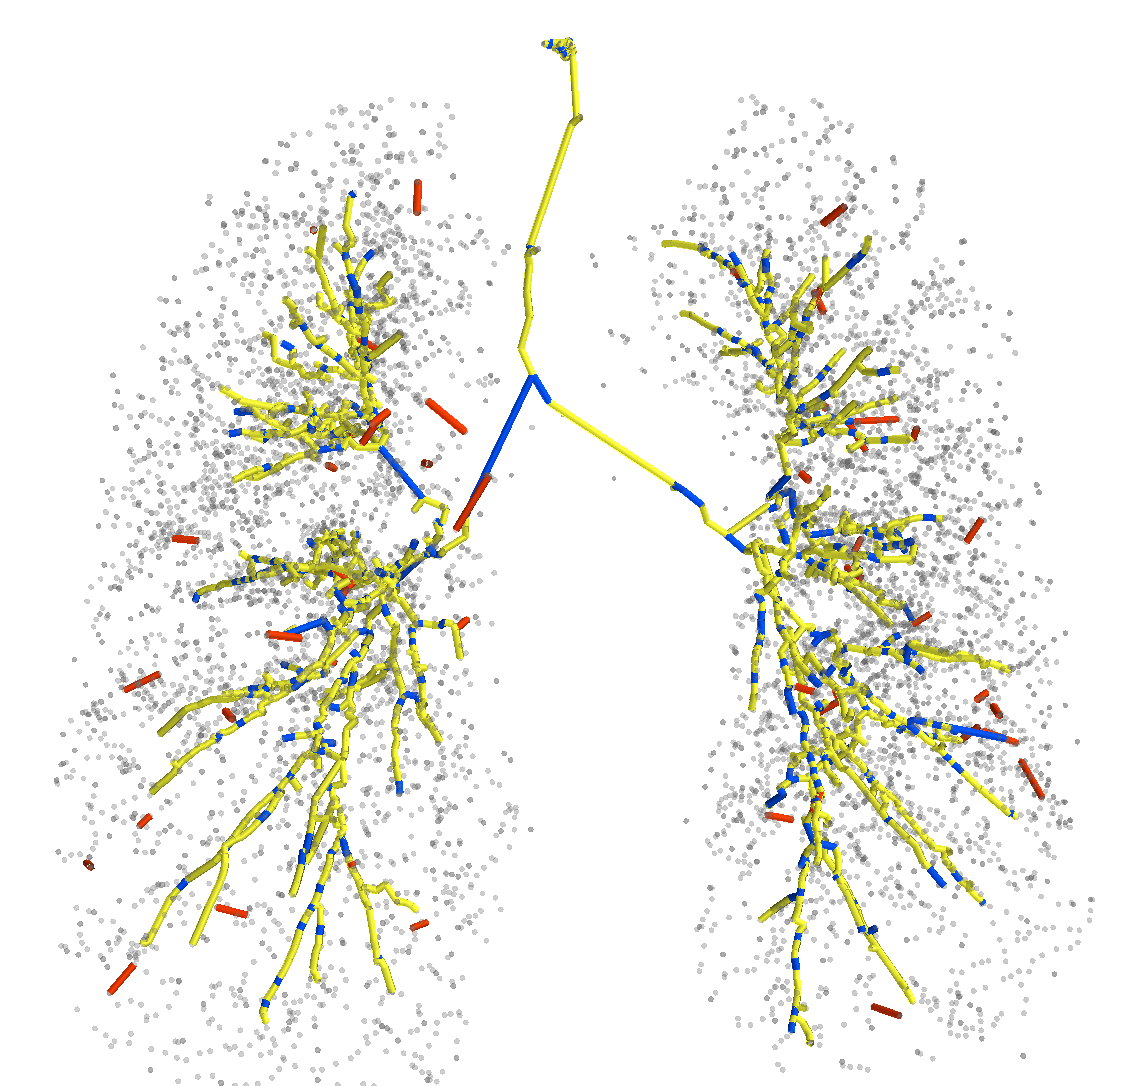

In Figure 2, first we present the predicted subgraph for one of the images. The gray dots are nodes of the over-complete graph with features, , extracted using Bayesian smoothing; the edges are colour-coded providing an insight into the performance of the method: yellow edges are true positives, red edges are false positives and blue edges are false negatives compared to the ground truth connectivity derived from the reference segmentations. Several of the false negatives are spaced closely, and in fact, do not contribute to the false negative error, , after generating the binary segmentations. The figure to the right in Figure 2 shows four predicted centerlines overlaid with the reference segmentation and centerlines from the voxel-classifier approach. Clearly, the MFN method is able to detect more branches as seen in most of the branch ends, which is also captured as the reduction in in Table 1. Some of the false positive predictions from MFN method appear to be a missing branch in the reference as seen in the first of the four scans. However, there are few other false positive predictions that could be due to the model using only pairwise potentials; this can be alleviated either by using higher order neighbourhood information or with basic post-processing. The centerlines extracted from MFN are slightly offset from the center of airways at larger scales; this could be due to the sparsity of the nodes at those scales and can be overcome by increasing resolution of the input graph.